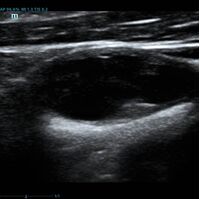

Помимо базовых целей по выявлению атеросклероза, бляшек, оценки кровотока и значимости стеноза, врачу ультразвуковой диагностики ставится и множество других задач при исследовании сонных артерий. Одна из них – оценка стабильности бляшки.

Ранее коллеги опирались на визуальную оценку, насколько бляшка гомогенная и какова её эхогенность. Есть ли в ней кальцинаты или анэхогенные участки. Для этого использовались международные классификации, с разделением среза бляшки по процентам – сколько гипер- и сколько гипоэхогенных зон. Такой метод  оценки до сих пор весьма популярен, однако он имеет минусы. Основной его минус в субъективности. Тяжело на глаз сказать, на 49,9% своей площади бляшка эхогенна или же на 50,1%, да и глаз у каждого человека несколько разный. Один специалист скажет – тут больше 50% гипоэхогенного, другой, что менее. Таким образом, метод сильно зависит от оператора – специалиста ультразвуковой диагностики.

Современное решение – компьютерный анализ структуры бляшки. Ультразвуковая система экспертного класса Mindray DC-8 способна провести программный анализ полученного изображения бляшки и дать количественную оценку её структуры. Для этого используется показатель GSM – Grey Scale Median. Прибор рассчитывает медиану по показателям серой шкалы в выделенной зоне и выдает данные в виде графика распределения эхогенности и числовых данных для количественной оценки. Таким образом, исследование становится более объективным и воспроизводимым, снижается зависимость от оператора (человеческого фактора).